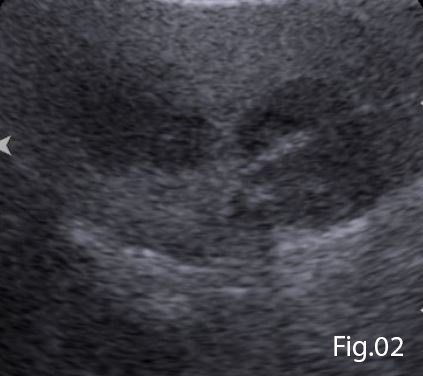

A Bolus of 2.4ml of SonoVue (Bracco, Milan) was administered through a cannula situated in the left antecubital fossa, followed by a 10ml bolus of saline solution. Both abscesses demonstrated peripheral enhancement with no uptake seen in the central fluid components (Figure 3). On further evaluation of the anterior gallbladder wall CEUS demonstrated a well-defined avascular defect providing a communication of the gallbladder contents with the adjacent hepatic abscess (Figure 4). These findings were conclusive of gallbladder wall perforation. A subsequent Computed Tomography confirmed this gallbladder perforation and hepatic abscess formation within segments V and V/VIII of the liver.

CEUS with its purely intravascular nature and exceptionally high spatial and temporal resolution (2,6) is a useful adjunct to B-mode ultrasound in cases of suspected gallbladder perforation (1). The use of contrast allows clear delineation of the avascular defect caused by the discontinuity of the gallbladder wall. Gallbladder wall defects are easily appreciated both on real-time and static imaging.